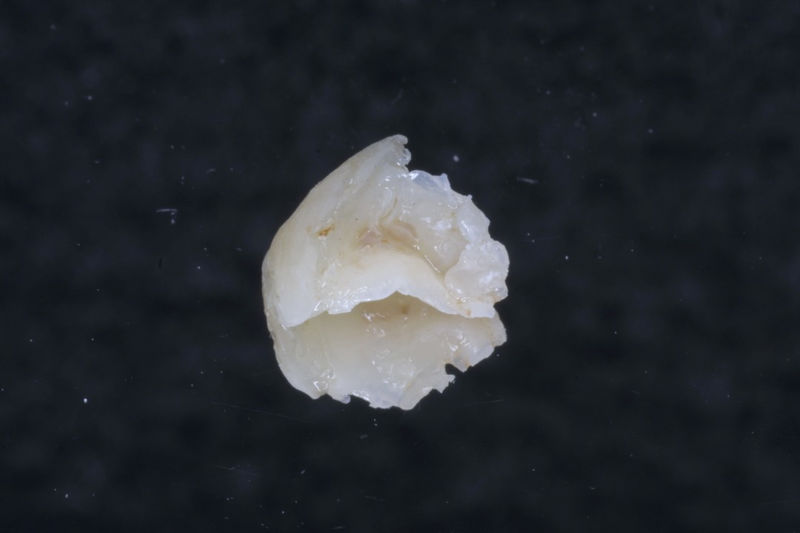

Implante fracasado, extracción, carillas, coronas y prótesis fija.